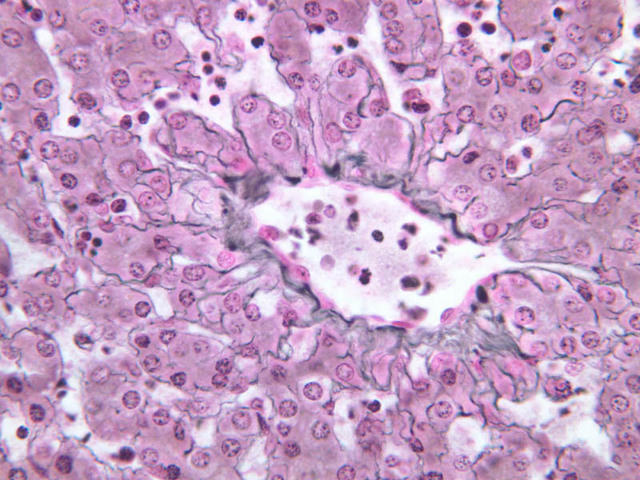

Although H & E staining permits ready identification of the islets of Langerhans, it does not permit differentiation of the various cell types that comprise the islets (B-36, H&E [10x, 20x, 40x-labeled]). There are no slides in the class collection that permit identification of all of the cell types of the endocrine pancreas. However, the sections on slides B-37 and B-40 permit specific identification of two cell types. Slide B-37 has been stained by the aldehyde fuchsin technique, which lends a magenta coloration to the granules of the insulin-producing B-cells. All other cells in the islets stain a dirty orange color (B-37 [10x, 20x, 40x] [10x, 20x, 40x]). Most of these orange-colored cells are the glucagon-secreting A-cells; however, you should bear in mind that somatostatin-secreting D-cells, as well as APUD cells that secrete pancreatic polypeptide are also scattered about the islet. The section on slide B-40 has been prepared by a silver impregnation method that renders some of the APUD cells in the islets (which appear as “clear cells” in ordinary preparations) dark brown or black (B-40 [10x, 20x, 40x]).